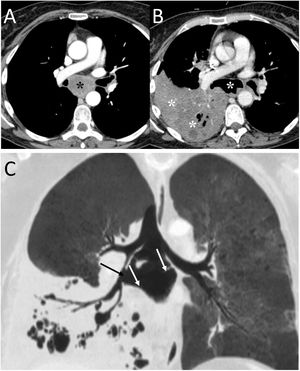

The most common acquired oesophago-respiratory fistula are tracheo-oesophageal and can be seen in 5%–10% of advanced oesophageal neoplasms, especially after radiotherapy15 (Fig. 5). Clinically, they can manifest as coughing attacks with fluid intake, dry mouth, neck and chest pain, spontaneous cough and sputum with food remains.15 Chest X-ray is non-specific. Endoscopy can identify the fistula and CT can determine the location and extent of the fistula, its cause and the status of the pulmonary parenchyma.15

A 58-year-old man with fever and dysphagia. A and B) The computed tomography showed an oesophageal wall thickening (white asterisk) and a fistulous path between the oesophagus and the intrathoracic trachea, clearly visualised when oral contrast was administered (white arrows). C) In the pulmonary parenchyma window, pulmonary consolidation was visualised in the right upper lobe (black asterisks). The radiological findings indicated an oesophageal neoplasm with tracheo-oesophageal fistula and aspiration pneumonia in the right lung. The patient was treated by placing an oesophageal endoprosthesis, with significant clinical improvement.

Bronchial perforations and tracheo-oesophageal or broncho-oesophageal fistulas can be caused by a ruptured lymph node. If the cause is infectious, it may be due to tuberculosis, histoplasmosis or actinomycosis.17 Bronchial perforation due to tumourous subcarinal adenopathies has also been described18 (Fig. 6). CT is helpful in revealing PM and the underlying cause.

A 48-year-old man with lung neoplasia treated with surgery and chemotherapy. A and B) The computed tomography (CT) scan showed the presence of a subcarinal adenopathy (black asterisk) that in the next control CT scan necrotised and filled with air (white asterisk). In addition, a right lower lobe lung consolidation was seen due to aspiration pneumonia (white asterisks). C) MinIP reconstruction (coronal plane) revealed a fistula between the intermediate bronchus (black arrow) and the necrotic adenopathy (white arrows).